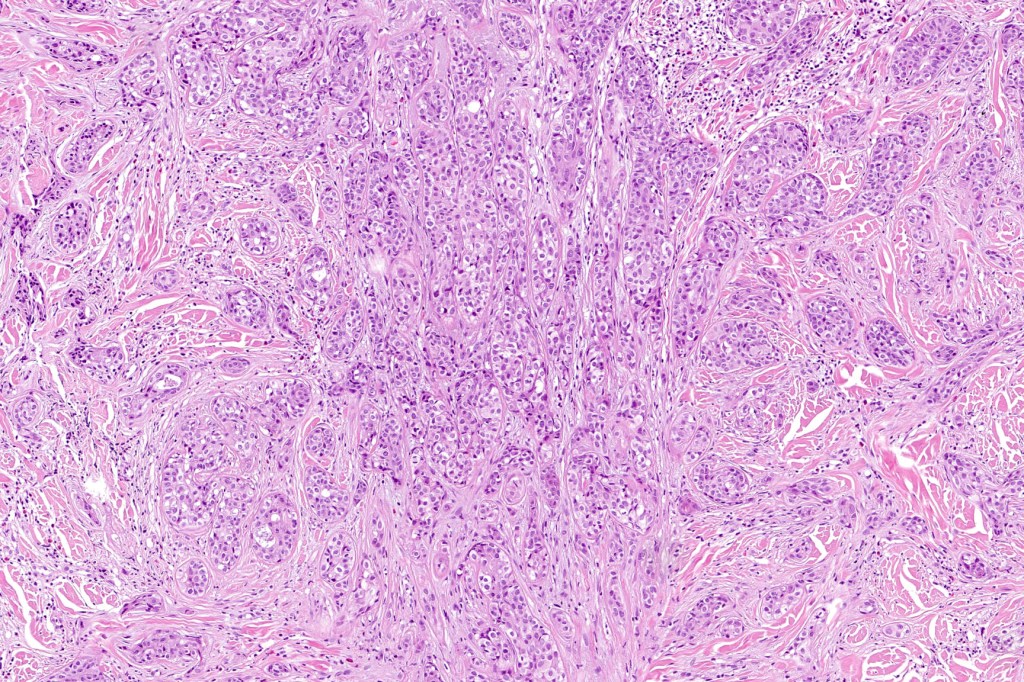

•Widely infiltrating biphasic tumor

•Adenocarcinoma in deeper reaches

•Variable pleomorphism and mitotic activity

•Deep part may show both ducts and glands

•Often extends to the subcutaneous fat

•Perineural infiltration is commonly seen